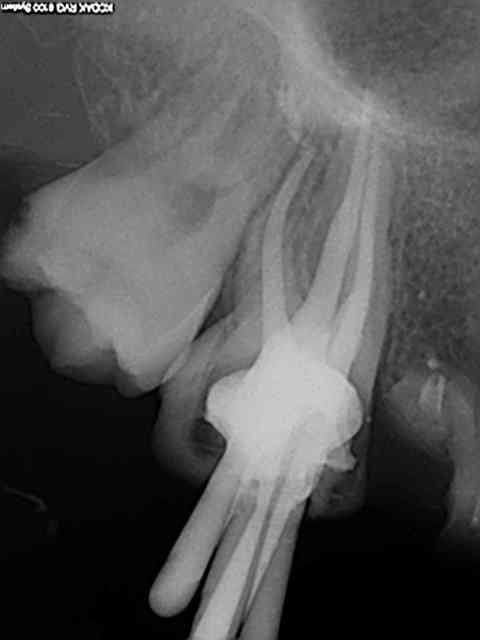

Comme celle là par exemple ? 20 ans et presque toutes ses dents )))) Mieux vaut avoir les radios initiales par les temps qui courent !